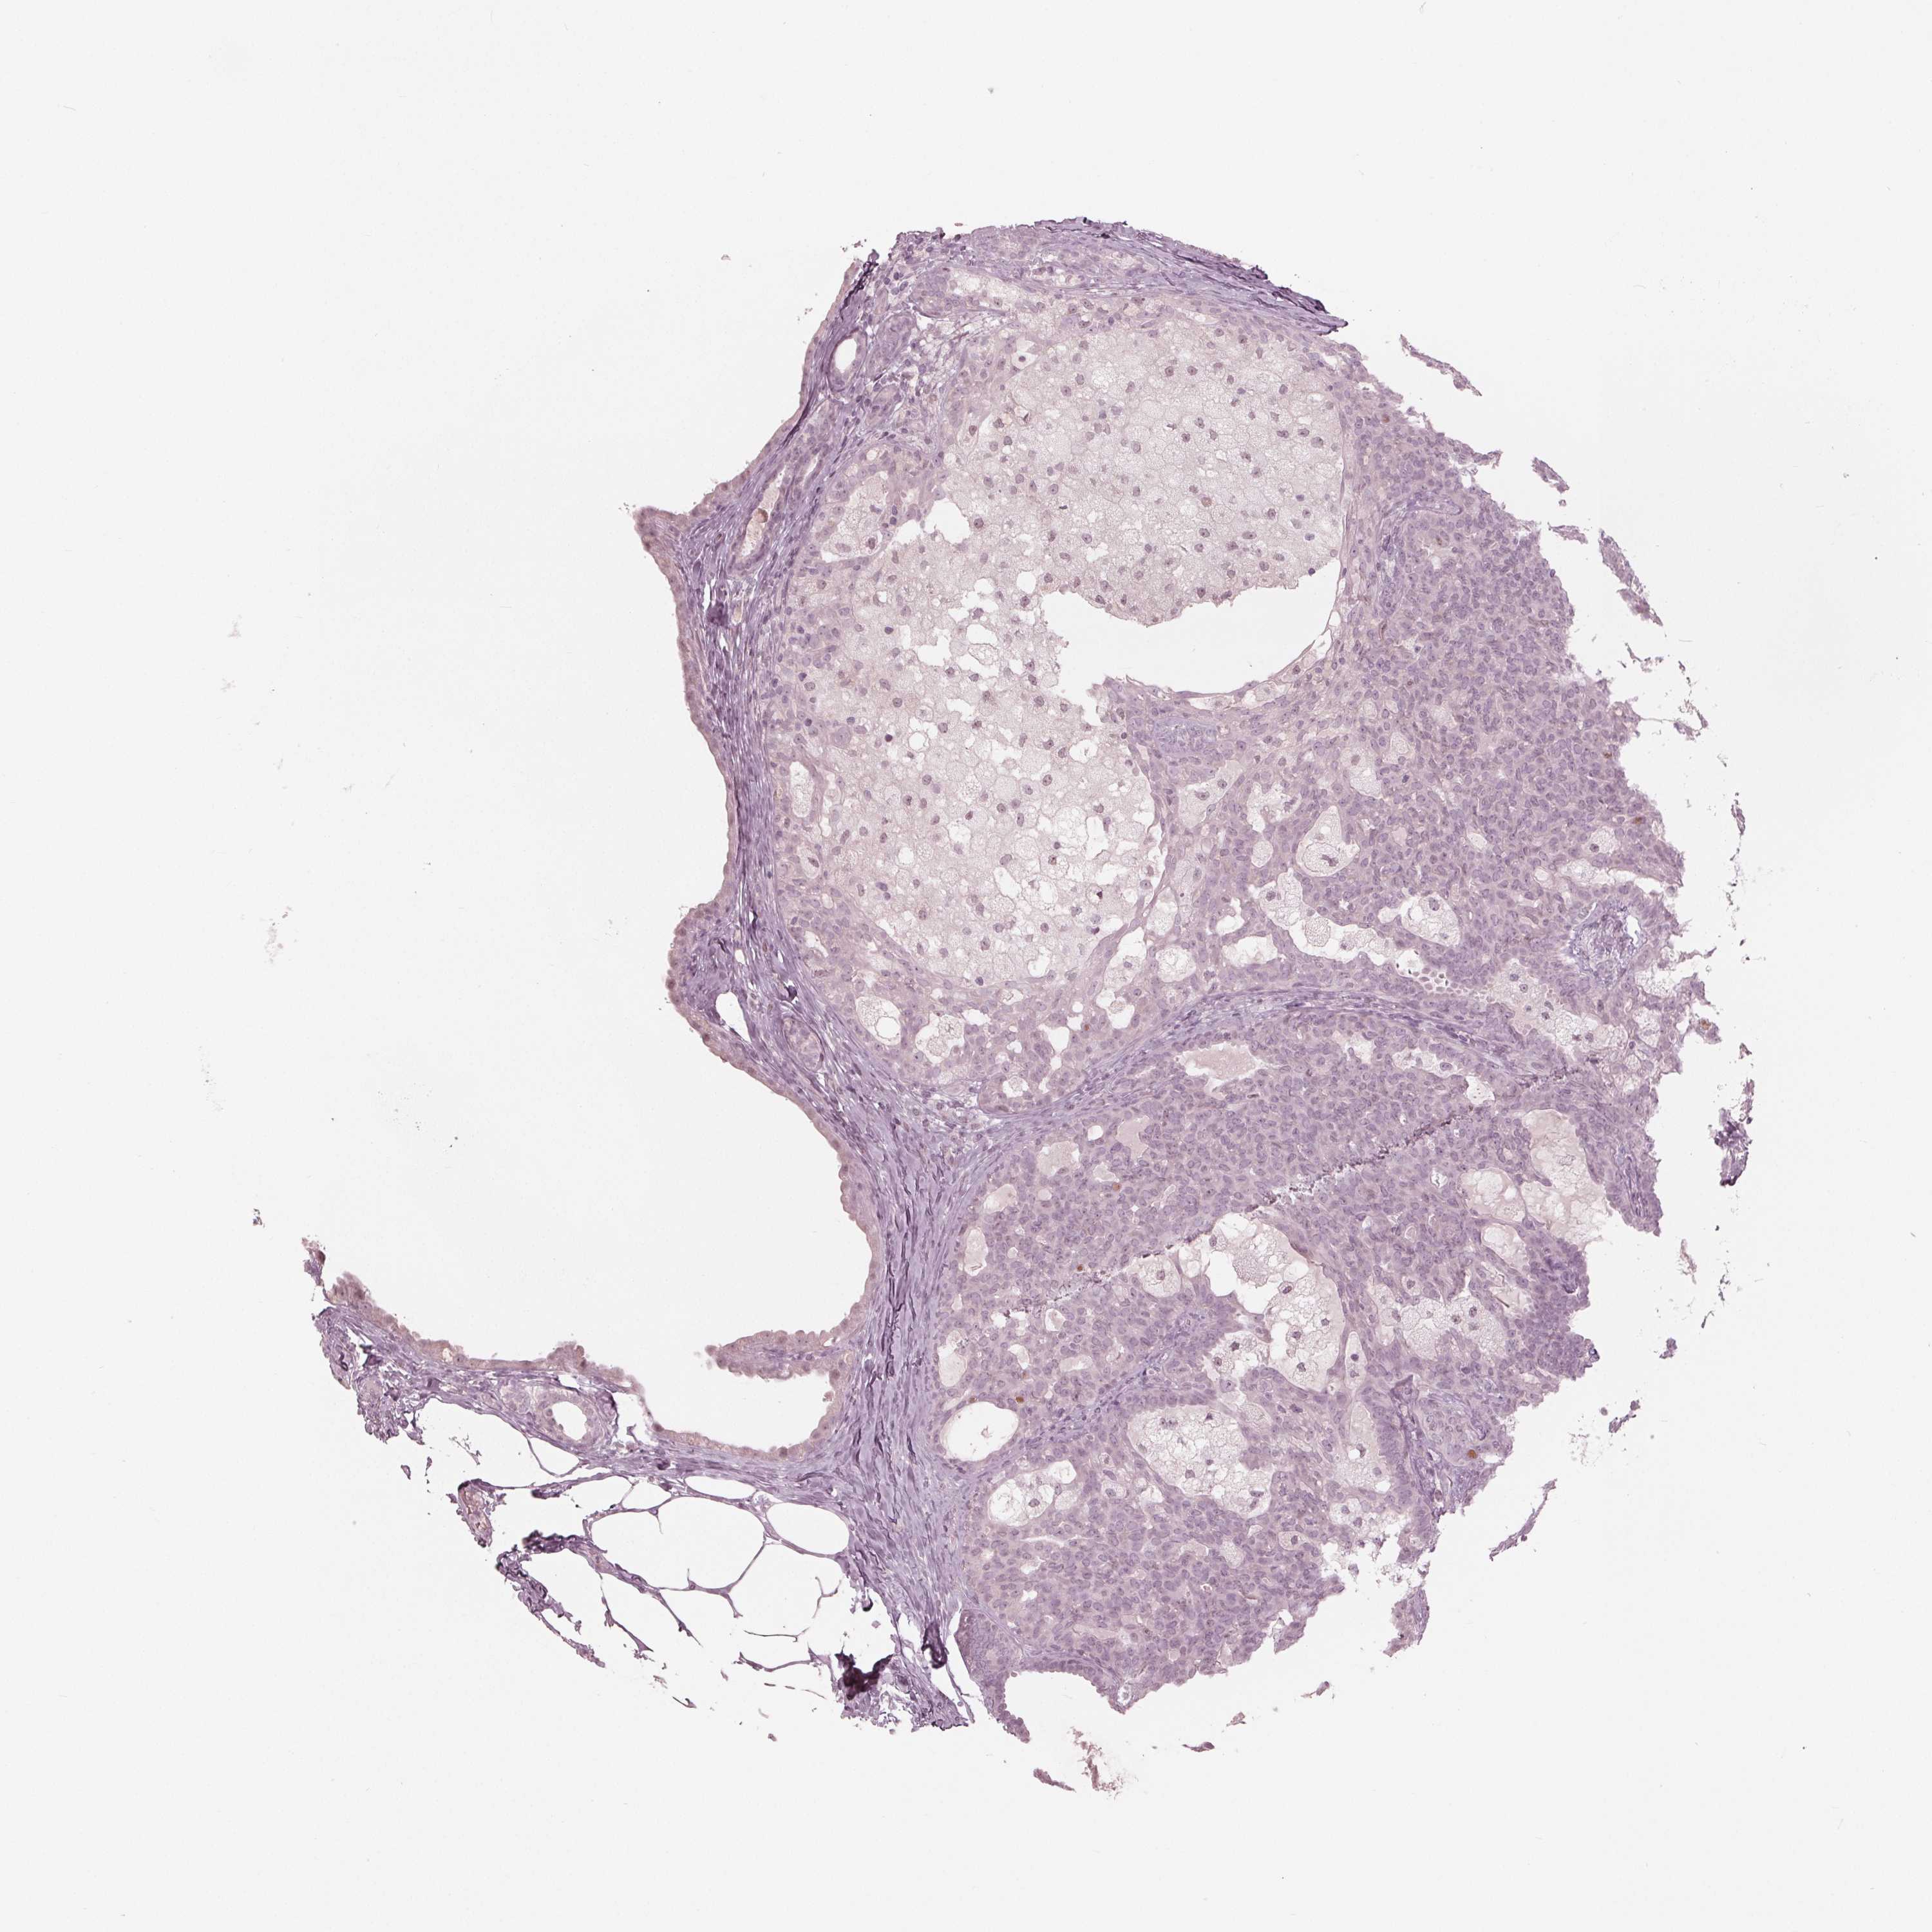

CANCER BREAST CANCER Show tissue menu

Breast cancer

Human cancer